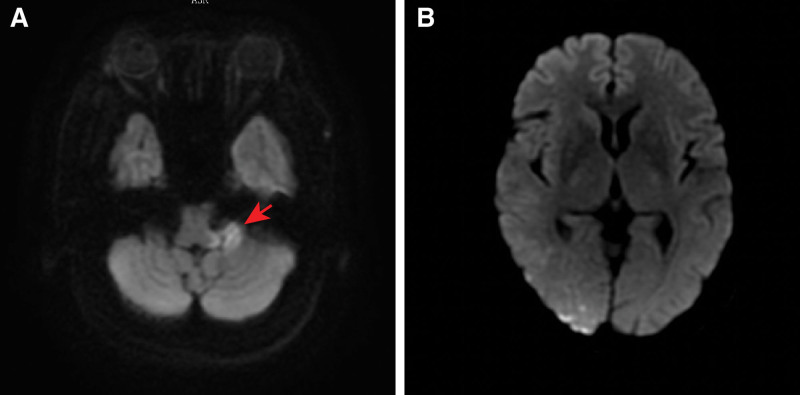

Figure 1.

Diffusion-weighted imaging (DWI) in the brain. (A) A high-intensity signal involving the left middle cerebellar peduncle; (B) several spotted areas in the right occipital lobe.

We describe a case of a 58-year-old hypertensive woman diagnosed with acute posterior circulation stroke who presented with persistent hiccups, sinus arrest, and post-hiccup syncope. Diffusion-weighted imaging revealed a high-intensity signal involving the left middle cerebellar peduncle and several spotted areas in the right occipital lobe.

A 58-year-old Chinese woman presented to the cardiology ward of our hospital with a 10-day history of vertigo, nausea, vomiting, occipital throbbing headaches, ataxia and a 6-day history of hiccups, sinus arrest and post-hiccup syncope. Ten days before admission, the patient experienced vertigo, nausea, vomiting, occipital throbbing headaches, tinnitus, hearing loss and ataxia, and the patient did not have any sensory deficits, limb dysmetria, language deficits or dysphagia. The patient went to the outpatient department for help, and the outpatient department failed to make a definite diagnosis. No significant abnormal results were found in abdominal ultrasound, gastroscopy, trans-cranial Doppler, carotid artery ultrasonography, vertebral artery ultrasonography, and a noncontrast head computed tomography (CT) scan. Six days before admission, the patient had syncope that was relieved for approximately 5 seconds. Five days before admission, the patient presented to the neurology ward of a military hospital. Diffusion-weighted imaging revealed a high-intensity signal involving the left middle cerebellar peduncle and several lacunar regions in the right occipital lobe (Fig. 1), which was consistent with the diagnosis of acute posterior circulation stroke. Magnetic resonance angiography suggested atherosclerosis, and no severe stenosis or occlusion was found (Fig. 2). Since then, the patient had recurrent episodes of hiccups and post-hiccup syncope every day. After recovery of consciousness, the patient had shortness of breath, which could be relieved in a few minutes. The electrocardiogram and blood pressure monitor exhibited sinus arrest and lowered blood pressure when the patient had the hiccups and syncope. The frequency of the patient hiccups and cough syncope gradually increased. All these factors led to the occurrence of depression, irritability and fear, affecting the patient diet and sleep. Therefore, the patient condition worsened each day. To ensure the safety of the patient life, the physicians placed a temporary pacemaker 3 days before admission. However, the patient hiccups still occurred several times a day, and they were accompanied by dysphoria but not syncope. Unfortunately, the patient developed fever, cough and expectoration 1 day before admission. To evaluate the causative diseases of arrhythmia and syncope, the patient was admitted to the cardiology ward of our hospital.